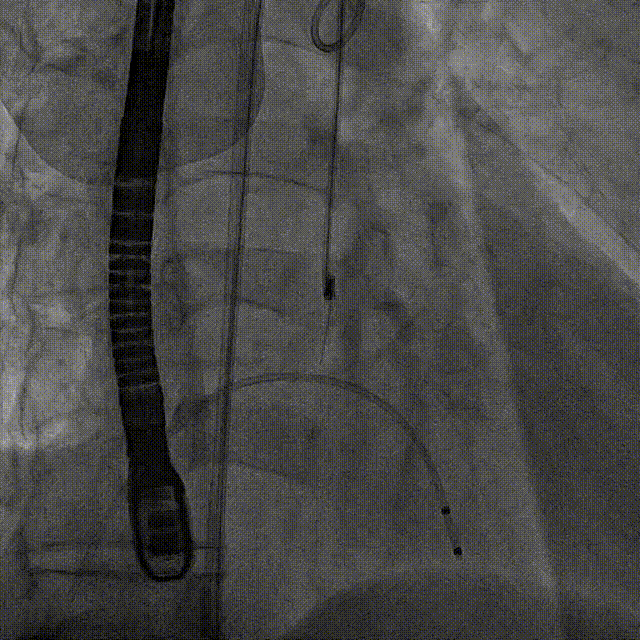

术中影像

后扩前

后扩

最终工作位置